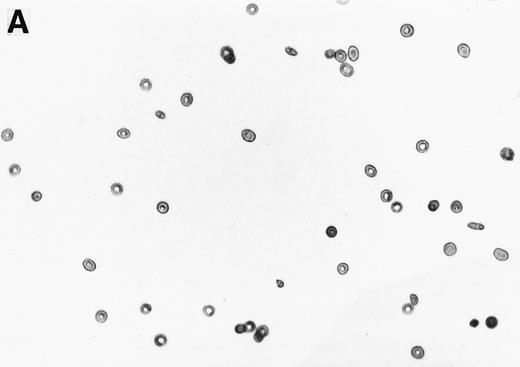

The 2% solution of light density cells in 10 mL of incubation buffer plus varying concentrations of reducing agents or antioxidants was placed in 50 mL volumetric flasks. The samples were incubated at 37°C, in a shaker water bath, with cycling of 15 minutes N2 followed by 5 minutes air for a total time of 16 hours. After 16 hours, the samples were flushed with O2 for 20 minutes, and aliquots were fixed with 1% glutaraldehyde. Blood smears were prepared and a minimum of 500 RBCs counted to determine percent ISCs. Cells with a length/width ratio of ≥ 2 were counted as ISCs. As can be seen in Fig 1, cells with multiple projections were rarely encountered. When they were encountered, they were not counted as ISCs. In some experiments, cyclic oxygenation-deoxygenation was followed by density separation as described above. In these experiments, each layer of the gradient containing RBCs was washed twice with PBS and the number of RBCs was counted using the Cell Dyn (Sequoia-Turner, Mountain View, CA).

Generation of ISCs after in vitro cycling. (A) Shows light density RBCs before in vitro cycling. (B) Shows SS erythrocytes after 16 hours of in vitro cycling in the absence of NAC. (C) Shows SS erythrocytes cycled in the presence of 20 mmol/L NAC with a reduction in the formation of ISCs.

Generation of ISCs after in vitro cycling. (A) Shows light density RBCs before in vitro cycling. (B) Shows SS erythrocytes after 16 hours of in vitro cycling in the absence of NAC. (C) Shows SS erythrocytes cycled in the presence of 20 mmol/L NAC with a reduction in the formation of ISCs.

NAC is an antioxidant and is converted intracellularly to L-cysteine, which is a precursor to reduced glutathione. We felt that the combined activities of this drug might make it particularly efficacious in blocking ISC formation in vitro. As shown in Table 2, NAC caused statistically significant decreases in percent ISCs at concentrations of 250 μmol/L to 20 mmol/L NAC. At 20 mmol/L NAC, there was a reduction of 35.7% ISCs. NAC (20 mmol/L) had no effect on cell lysis during the 16 hours of cycling, as evidenced by identical concentrations of hemoglobin (measured by absorbance at 430 nm) in the incubation mixtures ± NAC (data not shown). Figure 1 shows a typical smear of ISCs formed in vitro in the presence (Fig 1C) or absence (Fig 1B) of 20 mmol/L NAC.